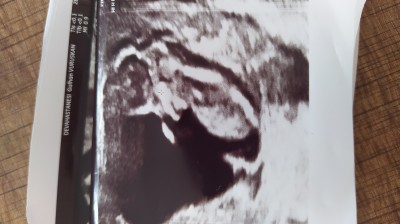

Merhabalar kızlar ben şu anda 15 haftalık hamileyim bu bu 12 haftalık ultrason fotoğrafı haftaya kontrole gidicez inşallah cinsiyetini de öğrenicez inşallah ama önce sizlerden tahmin almak istedim :)image

Kız gibi  geldı bana

Erkek bence  oturusundan belli

Kız gibi. Sağlıkla gelsin minnak <3